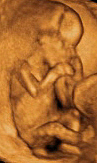

Desarrollo del feto en la semana 8: La vértebras crecen y rodean la médula

El bebé ha crecido de forma espectacular dentro del útero materno en lasemana 8 de embarazo. Mide entre 10 y 14 milímetros. A partir de esta semana, para los médicos ha dejado de ser un embrión y ha "ascendido" de categoría de feto. Su cabeza es muy grande en proporción al resto del cuerpo y siempre está inclinada sobre el cuerpo.